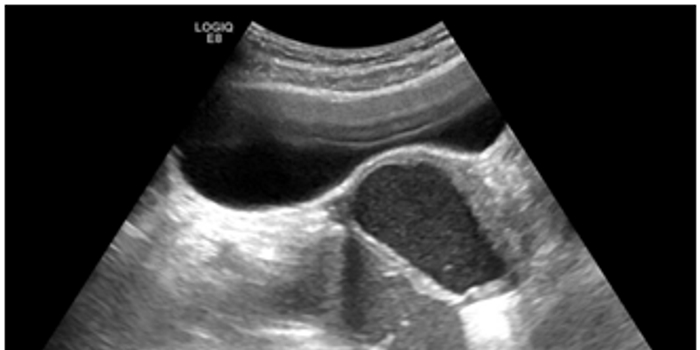

德州市第二人民医院超声医学科主任医师石洪柱接诊后为其进行了术前查体、定位,在超声引导下穿刺囊肿,抽出暗红色囊液,用生理盐水冲洗囊腔,聚桂醇硬化囊腔。做完第一个囊肿后,穿刺针不拨出体外,连续穿刺了第二个、第三个囊肿。每个囊肿在硬化后均保留3-5ml聚桂醇。整场操作娴熟流畅、全程无痛,治疗三个囊肿只在肚子上看到一个小针眼。术后,病理结果支持子宫内膜异位囊肿,让小丽感觉到前所未有的轻松。术后2个月复查,小丽患侧卵巢恢复正常,囊肿完全消失,疗效评价为治愈。